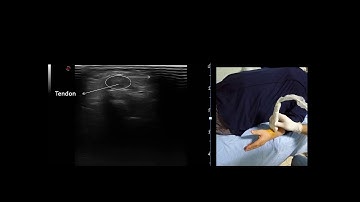

How to Scan & Inject DeQuervain's with Ultrasound